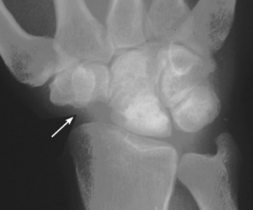

osteoarthritis

After a galley door slammed shut on his right wrist, a 37-year-old deckhand sought medical attention.